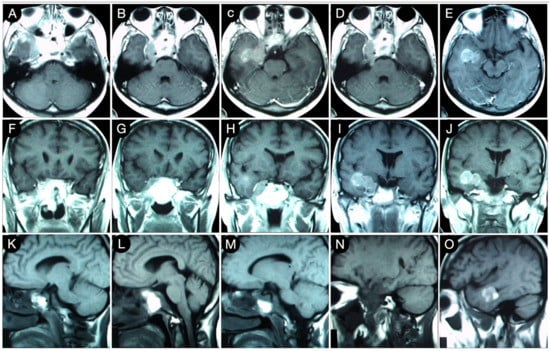

Case #8: Aggressive ACTH Tumor with Multiple Recurrences